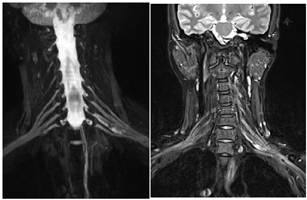

术后查体:左肘腕关节活动自如,左臂屈曲、外展可,神经感觉未见明显异常。术后肿瘤组织送病理检查,HE染色示神经鞘瘤。免疫组化结果:S100(+),SMA(-)。术后2周后未出现臂丛神经损伤症状及其他并发症,治愈出院。术后1周(图3)、1个月(图4)、半年(图5)、一年(图6)复查颈部MRI+增强及臂丛神经重建如下。